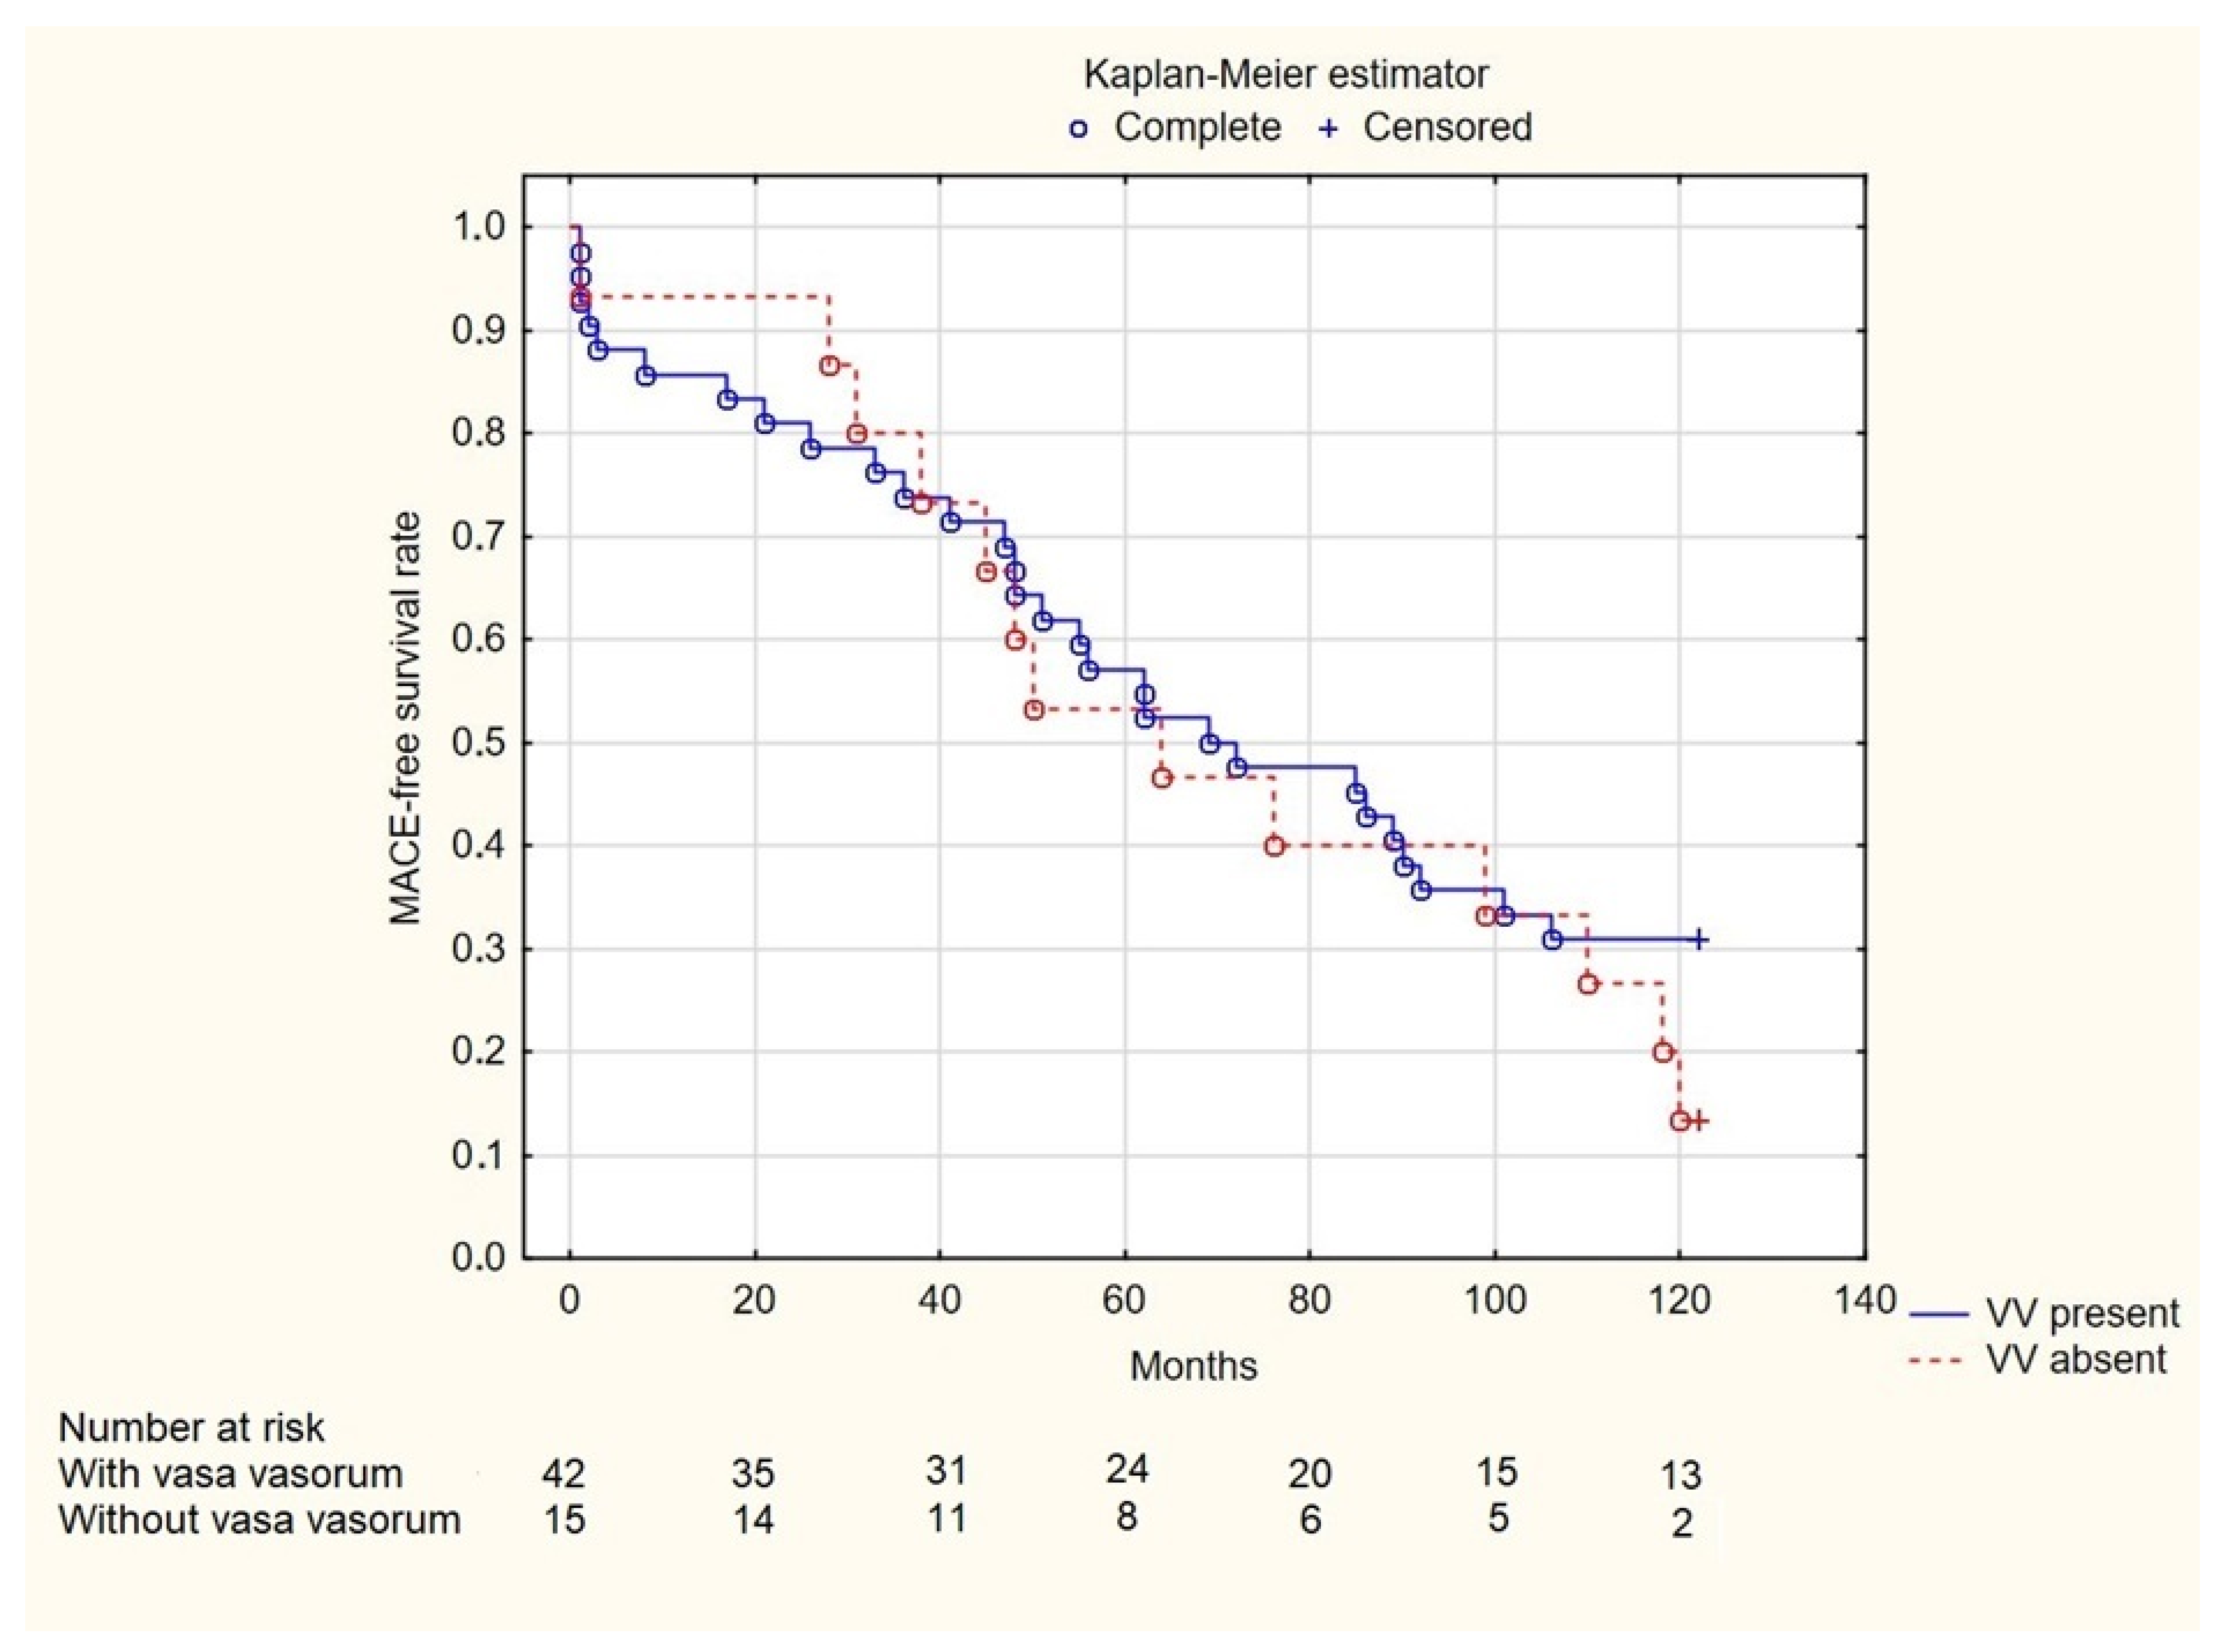

3. Results

4. Discussion

5. Conclusions